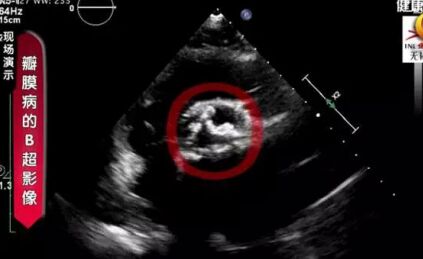

瓣膜病的B超影像

不正常的状态下,瓣膜会聚成一团,这个“门”打不开,也关不严,这个时候就会出现心脏的瓣膜病了。